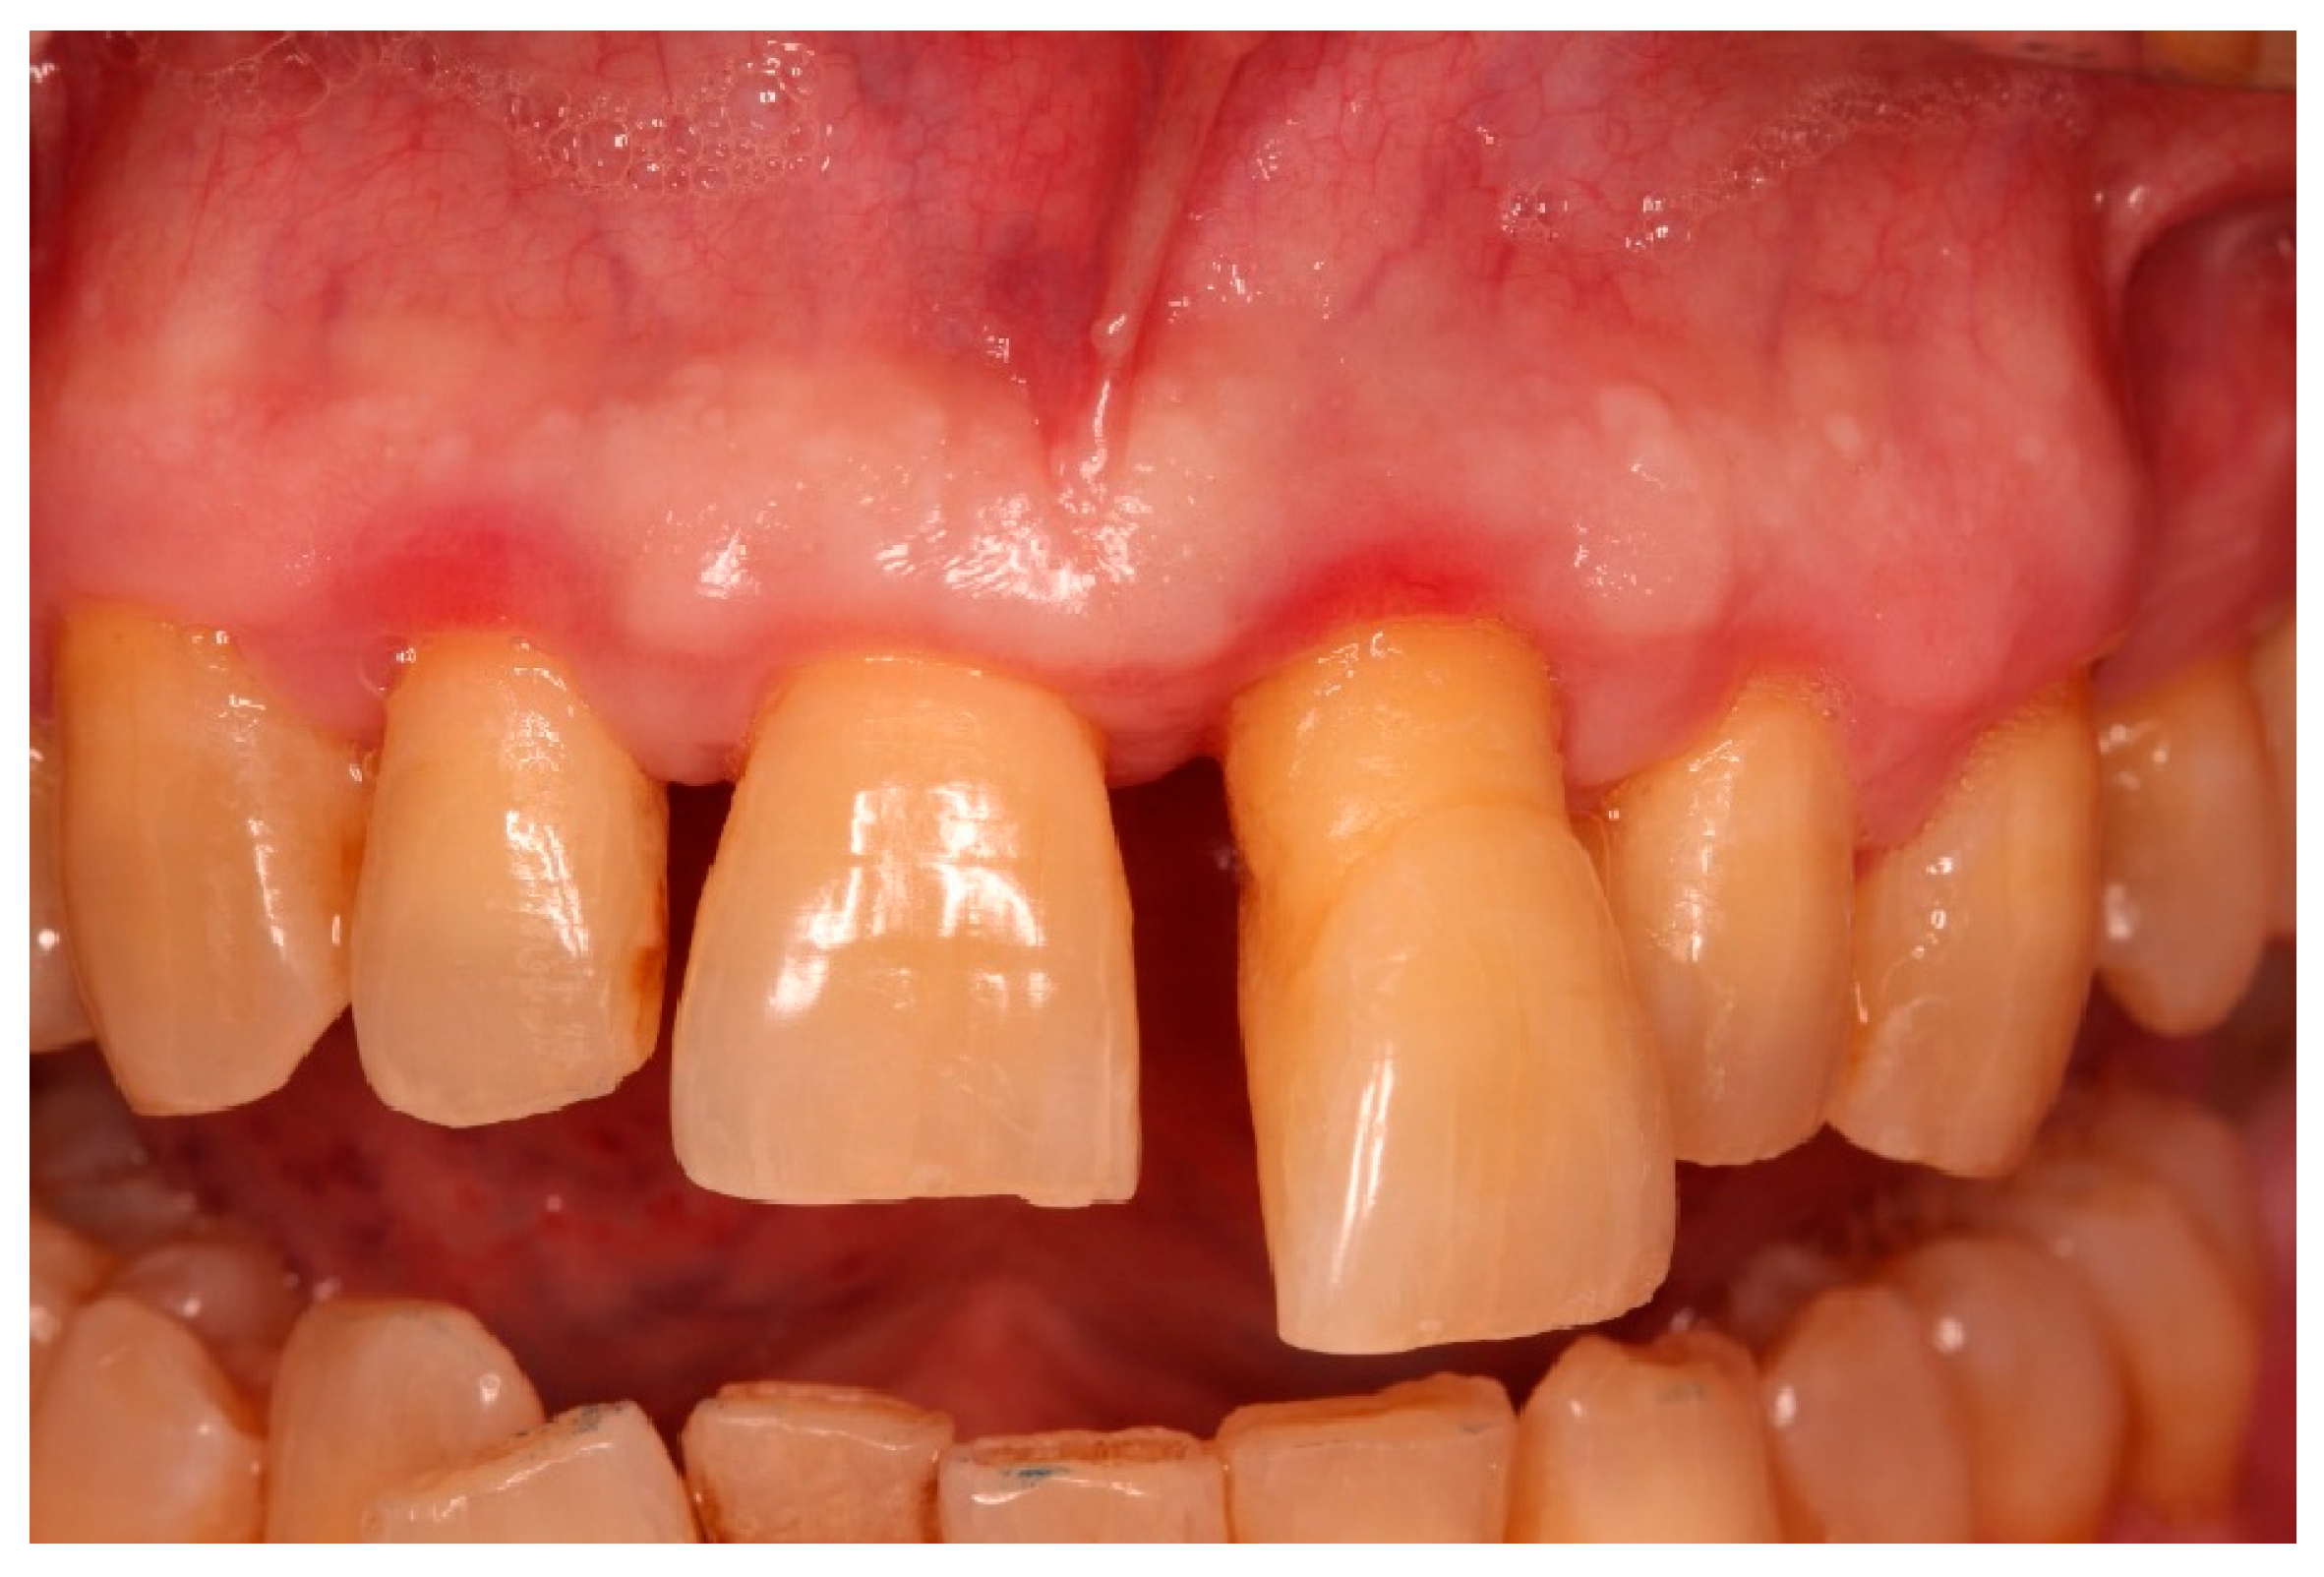

2.2. Patient Information and Periodontal Diagnosis

3.1. Clinical Findings

3.3. Functional and Aesthetic Outcomes